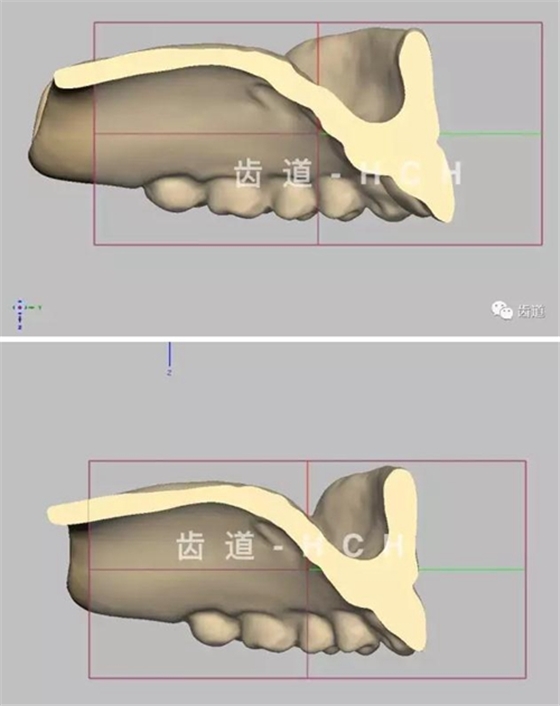

標(biāo)準(zhǔn)全口義齒模型截圖 科貿(mào)嘉友收錄